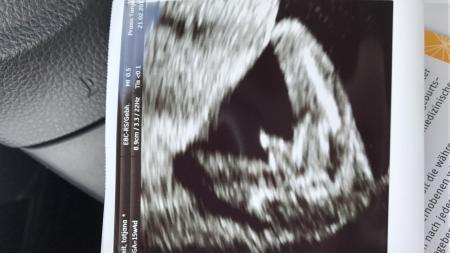

Ich finde es auch eindeutig:) so sah mein outing aus einer anderen Perspektive aus ;)

Bild zu